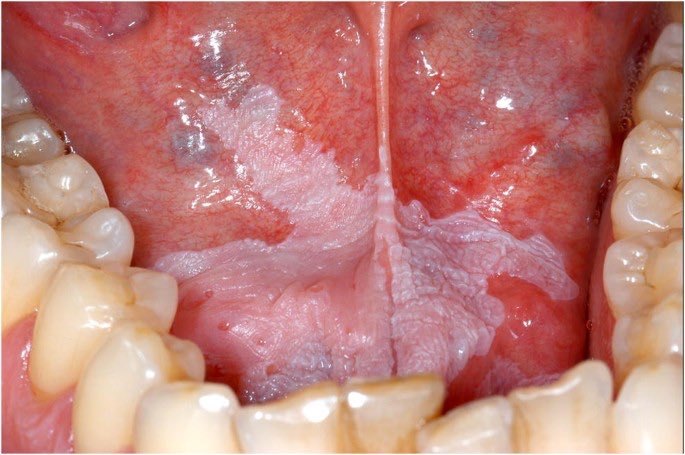

جروح بيضاء تتكون بسبب:

الشمّه/التمباك: الطبقة البيضاء تتكون في المكان اللي توضع فيه غالباً

التدخين: الحنك غالباً يكون مائل للون الابيض

الحل: التوقف عن التدخين والشمّه ومراجعة الطبيب باستمرار لقابلية هذي الجروح للتحول الى سرطان الفم واخذ عينة من الجرح اذا لم تتحسن